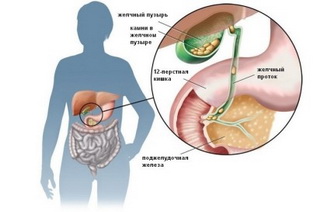

Стенки кишечника на 11 неделе беременности совершают первые перистальтические движения – начинается тренировка к перевариванию пищи после рождения.